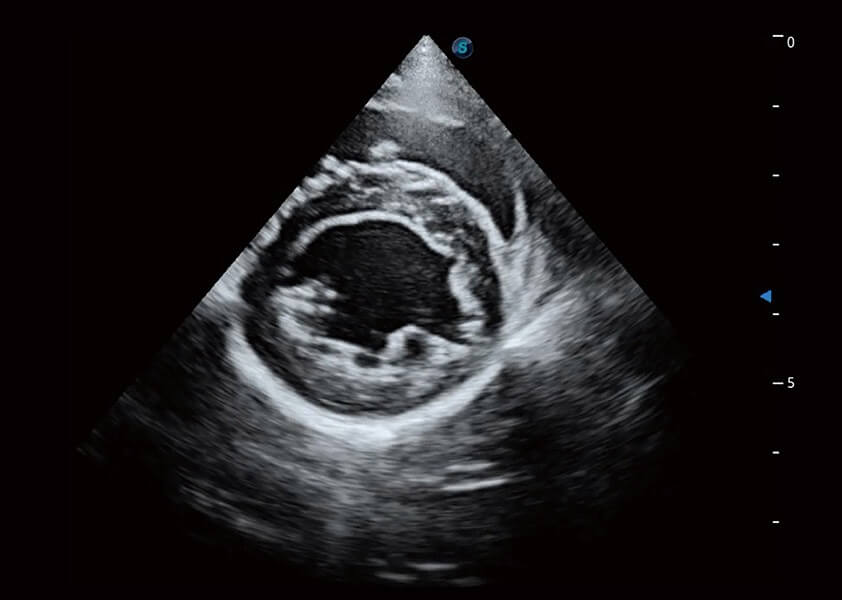

ProPet 60 作為一款高端臺式動物超聲設備,為動物醫(yī)生的日常診斷提供了一系列貼合動物臨床需求、解決臨床實際問題的高級成像功能。憑借全系列高清探頭,滿足醫(yī)生對腹部、心臟、生殖、淺表、肌骨等成像的所有需求,切實幫助您提升檢查效率,提高診斷信心。

動物是人類最親密的朋友和最值得信賴的伙伴。開立醫(yī)療也一直致力于探索動物專用的超聲影像解決方案。 全新推出的ProPet系列,是開立在動物超聲影像智能化、專業(yè)化、精準化的一次跨越式革新。動物不能用言語來表述自己的不適,通過超聲影像,ProPet系列搭建了動物醫(yī)生與不同物種溝通的“橋梁”,為動物醫(yī)生注入了“治愈之力”。